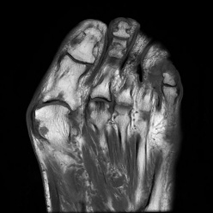

MRI(Magnetic Resonance Imaging/磁気共鳴画像)は、強力な磁石と電波を用いて体の内部を詳しく撮影する検査です。

放射線被ばくがなく痛みもない安全な検査です。通常20~40分程度で終わります。

脳だけでなく、全身のさまざまな部位の検査が可能です。

脳・脊椎・関節・四肢・腹部・骨盤・乳腺など幅広い部位に対応しています。

当院では最新の3テスラMRI装置を導入しており、従来の1.5テスラ装置とあわせて検査内容に応じた撮影を行っています。

3T MRIでは、高精細でより詳細な画像診断が可能です。